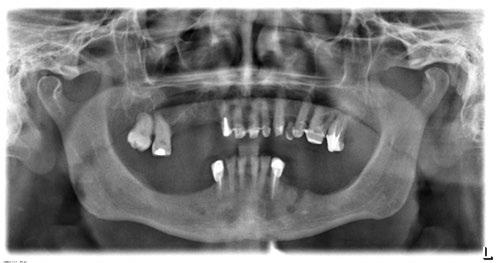

-Estudio radiográfico inicial (ortopantomografía y radiografías periapicales) (Figura 2).

A partir del estudio radiológico y de las imágenes fotográficas podemos observar edentulismo de 17, 15, 14, 12,

Figura 2. Ortopantomografía inicial.

25, 26, 28, 37, 38, 47 y 48. Presentaba corona desajustada en 13 con extensión en 12, implantes en 35-36, 45-46, con coronas ferulizadas en 35-36, 45-46, y dientes anteriores superiores con enfermedad periodontal Grado IV.